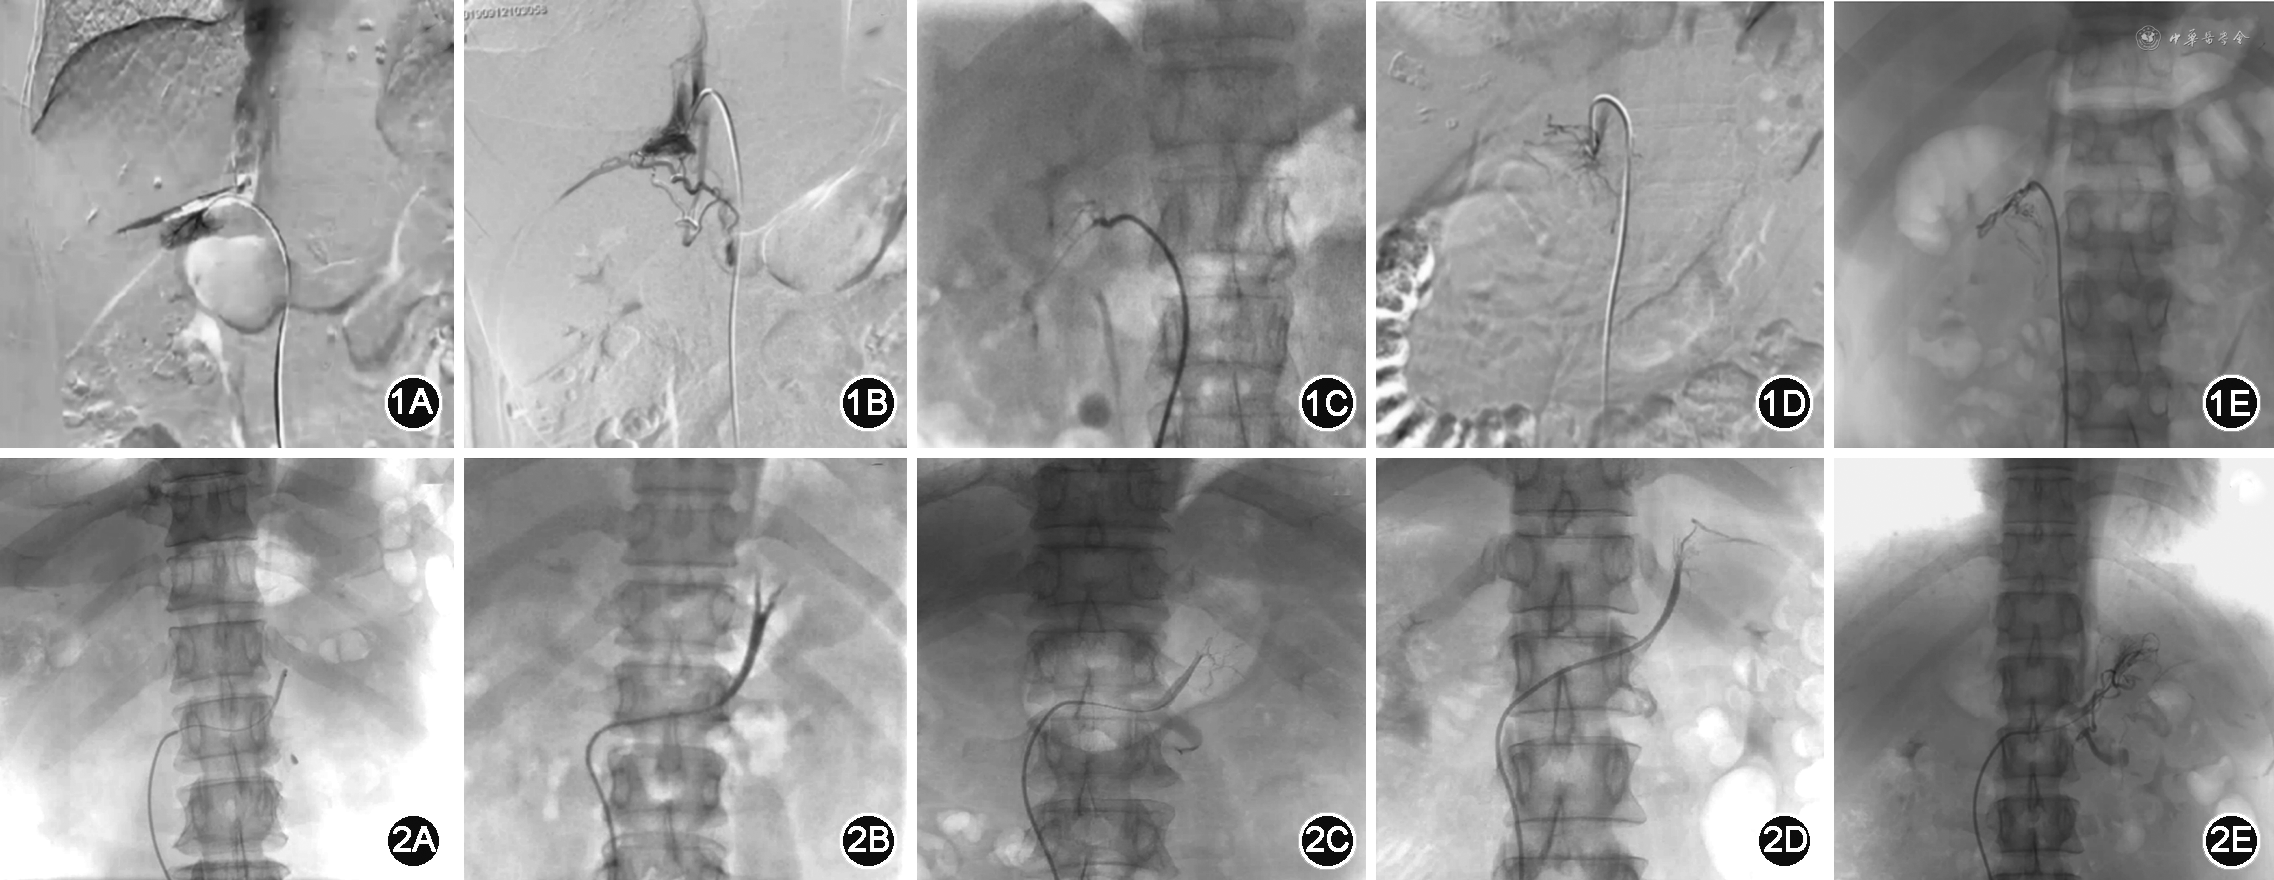

AVS采血的评价包括导管在位评估及取血成功。右肾上腺静脉造影形态包括腺体型、三角型、“△”型、蜘蛛型、不规则型(图1)。术中如右侧肾上腺静脉造影符合上述形态则认为右侧肾上腺静脉插管成功。左侧肾上腺静脉置管位置为左侧肾上腺中央静脉与左膈下静脉会合静脉或左侧肾上腺中央静脉,根据肾上腺静脉解剖位置可判断是否插管准确(图2)。

图3A~C示1例患者术前肾上腺增强CT经三维可视化处理后形成的图像,可见清晰的脊柱相应椎体、腔静脉、双侧肾上腺静脉及肾上腺静脉周围静脉血管的形态;D~F为肾上腺静脉采血术中造影的影像表现,双侧肾上腺静脉位置及肾上腺静脉周围血管形态均符合术前三维可视化处理所形成的图像。